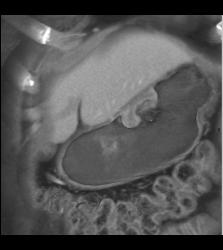

Bulky Tumor C/w Lymphoma Involving Stomach and Kidney